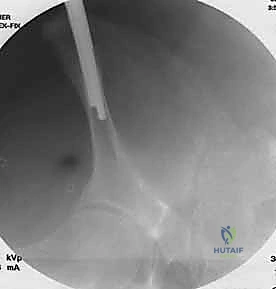

الخطوة الثانية: تحديد المعالم العظمية واستخدام الأشعة المرئية (C-Arm)

باستخدام جهاز الأشعة السينية المتحرك (Fluoroscopy) داخل غرفة العمليات، يقوم الدكتور هطيف بتحديد المعالم العظمية الدقيقة لضمان إدخال المسامير في الأماكن الأكثر كثافة وقوة في عظام الحوض (عادة فوق الحُق Supra-acetabular أو في العرف الحرقفي Iliac crest).

الخطوة الثالثة: إدخال المسامير المعدنية (Schanz Pins)

يتم عمل شقوق جلدية صغيرة جداً (حوالي 1-2 سم). من خلال هذه الشقوق، وبدقة متناهية لتجنب الأعصاب والأوعية الدموية، يتم إدخال مسامير معدنية سميكة ومصنوعة من التيتانيوم أو الفولاذ المقاوم للصدأ في عظام الحوض.